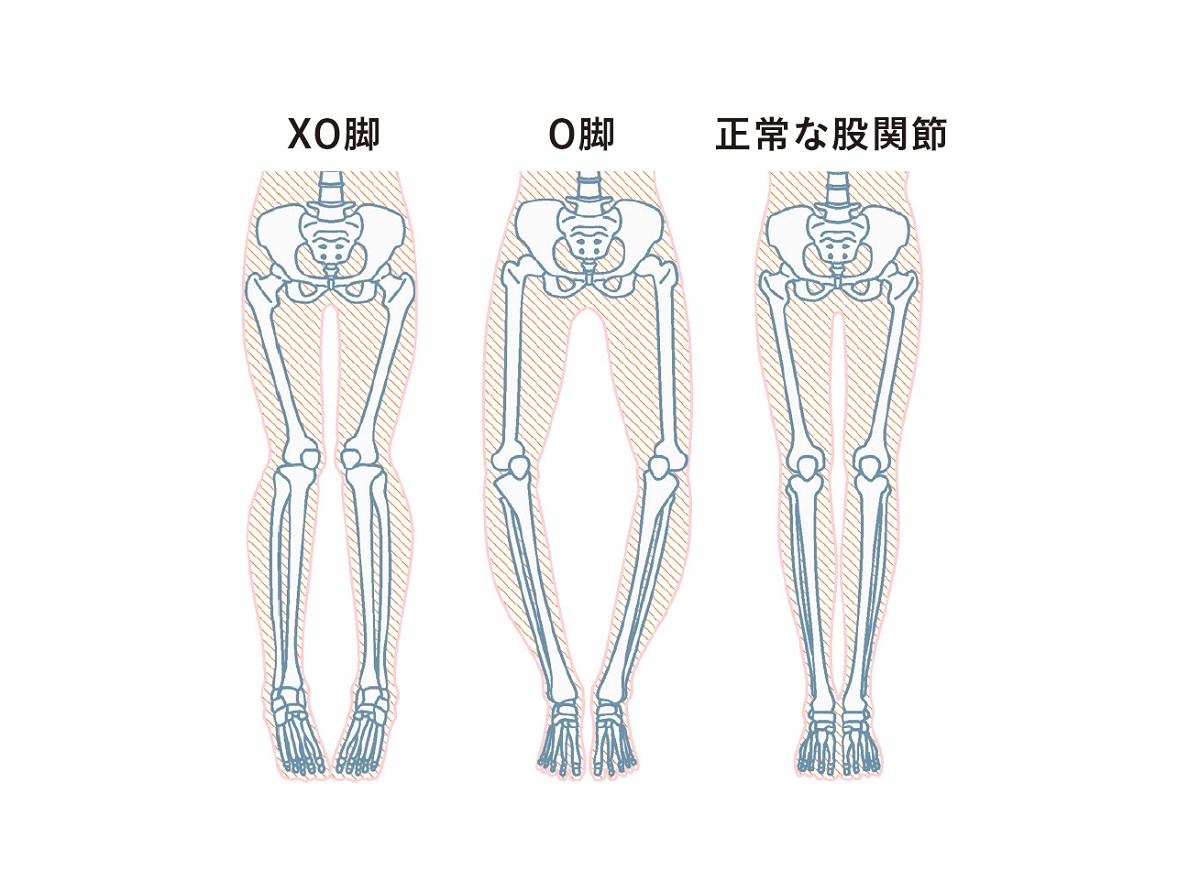

浮き指の下半身と骨の歪みの比較セットのイラスト素材

下半身の骨格の歪みのイラスト素材 8118

O脚の骨格 骨盤の歪み 脚の骨のイラスト素材

下半身太りの原因に 美脚の敵 内巻き股関節 とは Ananニュース マガジンハウス